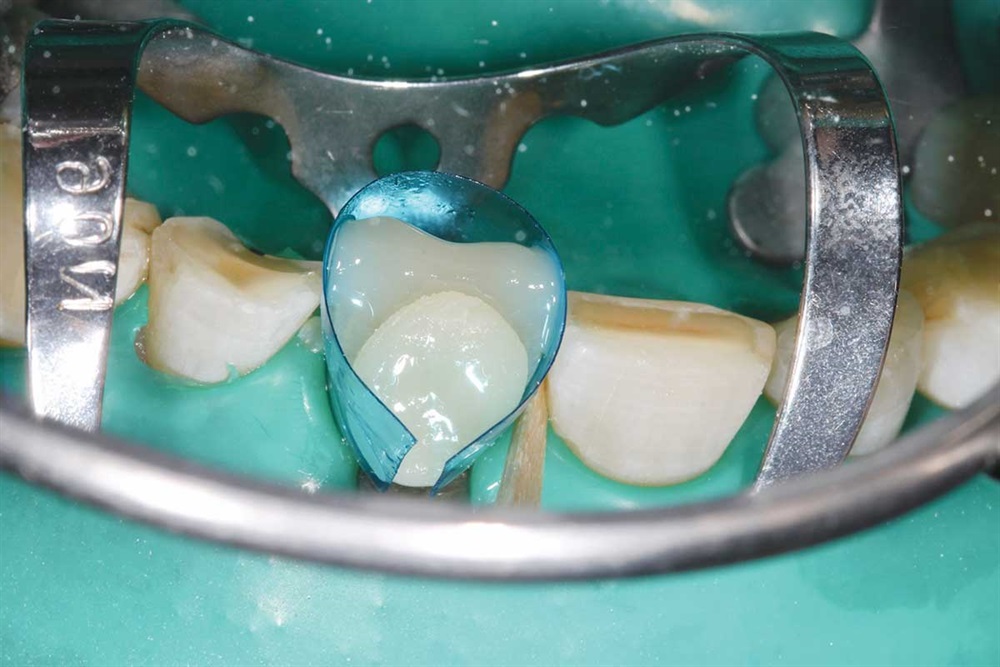

Fig. 7: Z250 A2 composite, AllBond 2 and Premier Dental Cure-Thru matrix bands were used.

Fig. 8: First tooth done, but not finished. I built up the incisors about 5mm.